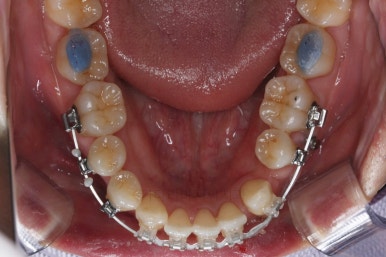

이 뽑은 자리로 앞니를 쭈욱 밀어넣으며 비대칭도 맞춰주기 위해서 미니스크류(마이크로 임플란트)라고 불리는 작은 나사를 잇몸뼈에 식립했어요.

이를 지지대로 삼아서 치아를 움직이게 됩니다.

아랫니를 계속 당겨주면서 가지런하게 하고 있어요.

아랫니 이 뽑은 자리는 거의 다 다물렸어요.

화살표는 사랑니인데요. 이 분의 경우 아래 앞니가 1개 없고, 1개를 추가로 뽑아서 윗니 대비 아랫니가 총 2개 모자란거죠.

운이 좋게도 이 분은 사랑니까지 잘 나와있던 상태라 내버려두기 아까워 함께 가지런하게 해주고 사용하실 수 있게 해드렸어요.